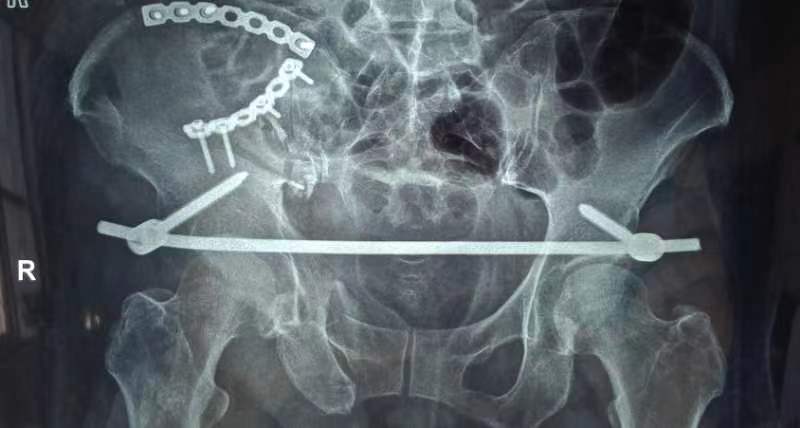

由于患者骨盆旋转和垂直不稳定,以及严重失血和肥胖,骨一科医疗团队进行讨论分析,决定采用微创内固定手术。8月25日成功完成手术,术后第二天患者能够在床上半靠,翻身时疼痛明显缓解,下肢功能恢复良好。

Infix(骨盆内固定支架)技术是一种最新的微创内固定方法,适用于治疗不稳定型骨盆前环损伤,尤其适合肥胖、腹部有手术刀口、体弱或有膀胱造瘘患者。该技术融合了内固定和外固定优点,通过透视下的精准操作和微创置钉,实现了骨盆环的稳定,使患者能够进行早期功能锻炼,最大程度降低了伤致残的风险。